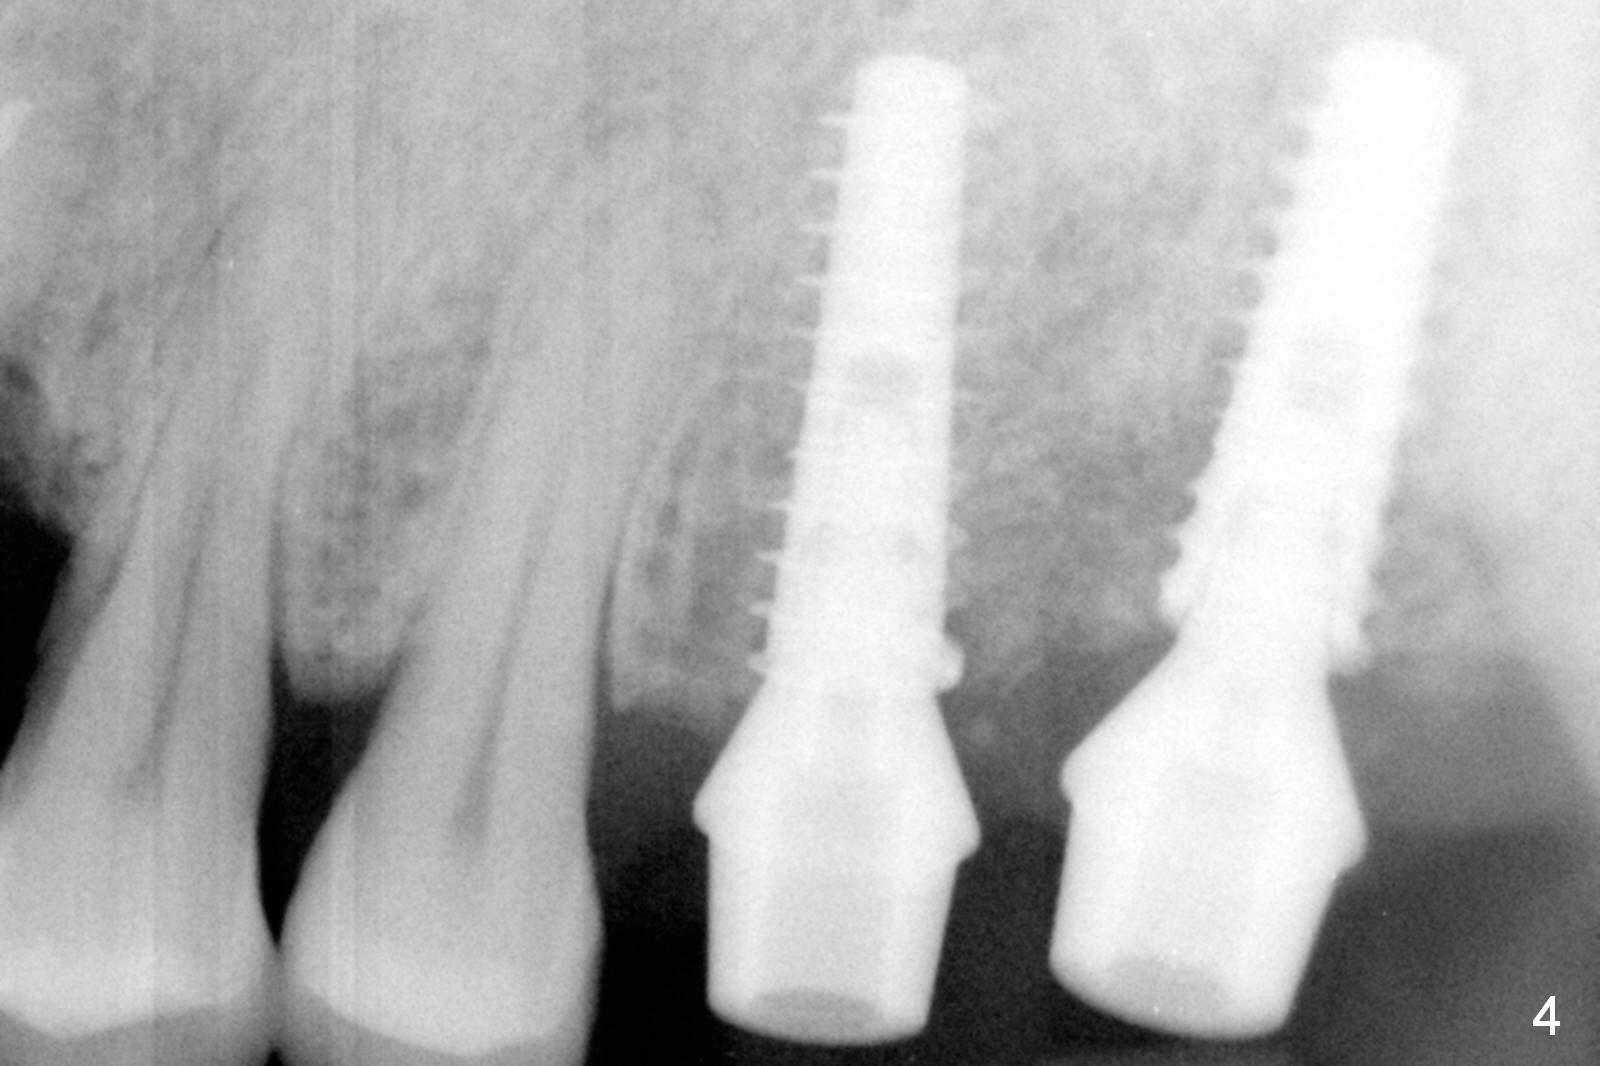

As shown by CT, the ridge at #14 is narrower than that of #15 (confirmed after incision), whereas the density at #14 is higher than that of #15. The osteotomies are established by combination of magic osteotomes and drills after change in trajectory (Fig.1-3). Following placement of 4.5x13 and 5x13 mm IBS implants and 6x4(3) and 6.5x4(3) mm pair abutments at #14 and 15 (Fig.4), flaps are sutured for hemostasis. Since the patient does not tolerate the surgery too well (unstable hypertension and oozing), immediate provisional is delayed. Periodontal dressing is applied instead. While the implants are healing, porcelain chips at the upper anterior bridge. There appears no bone resorption 6 months postop (Fig.5). Impression is taken following changing abutment to 5x4(2) mm at #14 and Diode gingivectomy. A panoramic film is taken 1 year 2 months post cementation. CT taken 2 years post cementation shows relatively good trajectory of these 2 implants (Fig.6,7).